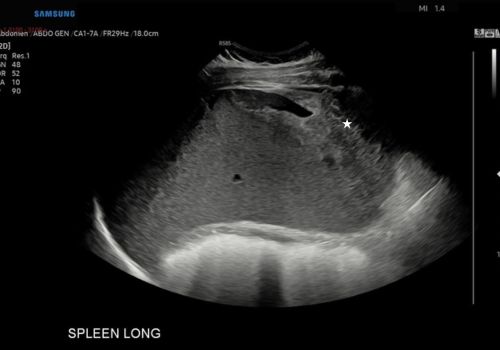

A heterogenous area with a small area of central fluid left subphrenic space surrounding/indistinct from the superior spleen was identified with no colour doppler flow.

Figure 2, 3 and 4 above; Heterogeneous area(star) with a small area of central fluid in the left subphrenic space surrounding and indistinct from the spleen (arrow)